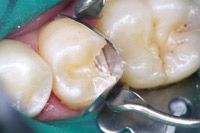

Excess liner was removed using hand instruments and the cavity preparation was etched, rinsed and coated with adhesive, which was air-thinned and light cured (Figs. 5 and 6).

Fig. 5

Fig. 6

The cavity preparation was matrixed (Fig. 7) and composite resin then syringed into the cavity preparation (Fig. 8).

Fig. 7

Fig. 8